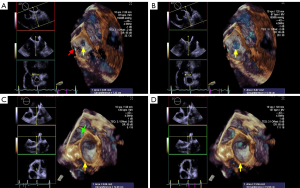

The LAA (Figure 2A,B,C,D, red arrowhead) can be seen in varying sizes during the different phases of the cardiac cycle (the yellow arrow points to the time frame of the cycle). As demonstrated in Figure 2, patients with long-standing AFib showed a different contraction and relaxation LAA morphology during AFib, noting that a coumadin ridge was found in the same patient (Figure 2, asterisk). LAA morphology parameters, including depth, orifice diameter, and orifice area should be strictly assessed in the same cardiac cycle. In order to discover more LAA details and differences between the two AFib classifications, these LAA morphology parameters were further collected and compared by RT-3D TEE. We found that the LAA orifice was markedly enlarged in long-standing patients, compared with paroxysmal AFib group (Figure 3, Table 3). The diameter of the LAA orifice was carefully measured from multiple angles, including the 45° and 135° views. The average systolic inner diameter of the LAA opening in the 135° view were 23.9±8.4 and 28.7±7.6 mm, in the paroxysmal and long-standing groups, respectively (P=0.03). The average diastolic inner diameter of the LAA opening in the 135° view were 19.3±8.9 and 24.0±10.1 mm in paroxysmal and long-standing groups, respectively (P=0.04). Meanwhile, there was no difference in terms of the LAA orifice diameter in the 45° view (P=0.05 in systole, P=0.13 in diastole). Long-standing AFib group patients also had a markedly greater value of LAA area in the systolic and diastolic phases compared with the paroxysmal group (P=0.01). However, the LAA depth did not differ significantly between them (30.2±13.6 vs. 32.4±15.8, respectively, P=0.43) (Table 3).